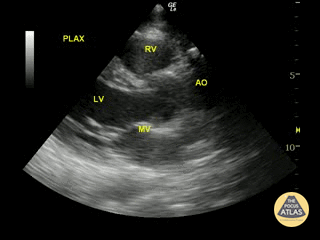

Normal Cardiac Anatomy - Normal Parasternal Long-Axis View